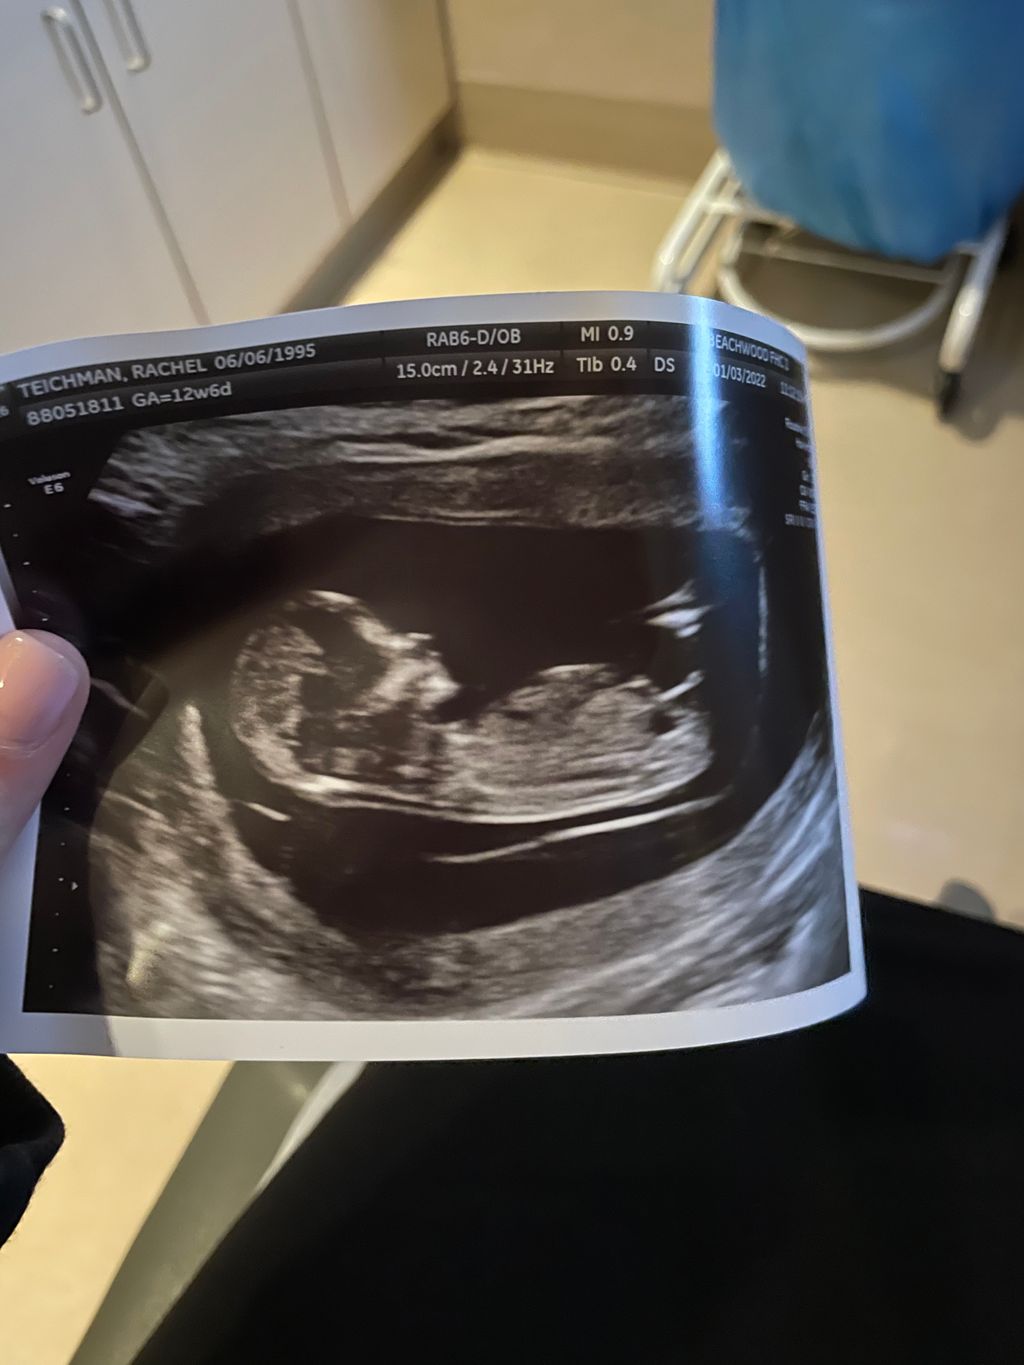

Boy Or Girl Baby Nub . when your baby’s nub (genital tubercle) is forming and visible around 12 weeks, the angle of the dangle can assist in predicting the sex of your baby. the nub theory is a fascinating and intriguing concept that explores the early development of genitalia during foetal growth. the nub theory is a medical term used by healthcare professionals to identify the baby's gender from around 12 weeks in gestation. The gender will usually be easier to predict if the nub is seen to be angled above 30 degrees or higher in. unlike other methods such as the chinese birth chart, or old wives' tales about pregnancy to guess if you're carrying a boy or a girl,. Inconclusive = 10° to 30°. The nub (genital tubercle) is. Nub theory says if you can get a good look at this nub on an. In the diagram, the horizontal line (0°) is the baseline (baby's lower spine). a boy nub in development varies at different gestation. the genital tubercle or “nub” is fetal tissue that will develop into a penis or a clitoris as the pregnancy progresses. boy = 30° or greater. Girl = 10° or less.

the nub theory is a medical term used by healthcare professionals to identify the baby's gender from around 12 weeks in gestation. In the diagram, the horizontal line (0°) is the baseline (baby's lower spine). the genital tubercle or “nub” is fetal tissue that will develop into a penis or a clitoris as the pregnancy progresses. Girl = 10° or less. Inconclusive = 10° to 30°. Nub theory says if you can get a good look at this nub on an. the nub theory is a fascinating and intriguing concept that explores the early development of genitalia during foetal growth. The gender will usually be easier to predict if the nub is seen to be angled above 30 degrees or higher in. a boy nub in development varies at different gestation. The nub (genital tubercle) is.

Boy Or Girl Baby Nub the nub theory is a medical term used by healthcare professionals to identify the baby's gender from around 12 weeks in gestation. the genital tubercle or “nub” is fetal tissue that will develop into a penis or a clitoris as the pregnancy progresses. In the diagram, the horizontal line (0°) is the baseline (baby's lower spine). The gender will usually be easier to predict if the nub is seen to be angled above 30 degrees or higher in. The nub (genital tubercle) is. a boy nub in development varies at different gestation. Inconclusive = 10° to 30°. unlike other methods such as the chinese birth chart, or old wives' tales about pregnancy to guess if you're carrying a boy or a girl,. boy = 30° or greater. the nub theory is a medical term used by healthcare professionals to identify the baby's gender from around 12 weeks in gestation. when your baby’s nub (genital tubercle) is forming and visible around 12 weeks, the angle of the dangle can assist in predicting the sex of your baby. Girl = 10° or less. Nub theory says if you can get a good look at this nub on an. the nub theory is a fascinating and intriguing concept that explores the early development of genitalia during foetal growth.